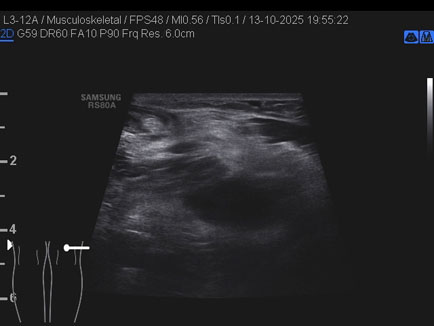

Data inserimento: 16/10/2025

Ecografia del: 13/10/2025

Strumento: Samsung

Sonda: Lineare

Commento all'esame: giovane atleta con referto di RMN che riporta cisti del semimembranoso/gemello e falda fluida lungo il gemello mediale medesimo.

Alla ETG:

A. formazione cistica di circa 22 x 17 x 23 mm (DAP x DT x DL = 4.5 ml) indovata tra il semimembranoso ed il gemello mediale: borsite dei tendini suindicati; assenza di falde fluide a carico dello sfondato sottoquadricipitale!

B. rottura completa del semitendinoso in sede distale con diastasi dei monconi di circa 25 mm.

Conclusioni: lesione e cisti del muscolo semitendinoso destro (right semitendinosus muscle injury and cyst).